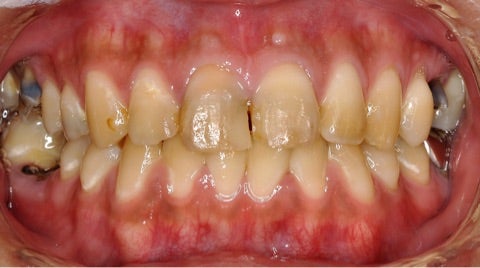

本日は歯科恐怖症の為、奥歯の虫歯を放置してしまい、だんだんと前歯も欠けて日に日に見栄えが悪くなって来た…

▶︎患者様は「最近どんどん歯がボロボロになってきている」と仰っていました。

一見歯の状態はそこまでボロボロには見えませんが、実は奥歯の状態が特に悪く、痛みもあり食事はほぼ前歯を使用している状態です。

その結果前歯へのダメージが蓄積し、着色や欠けが目立つようになってきてしまっています。